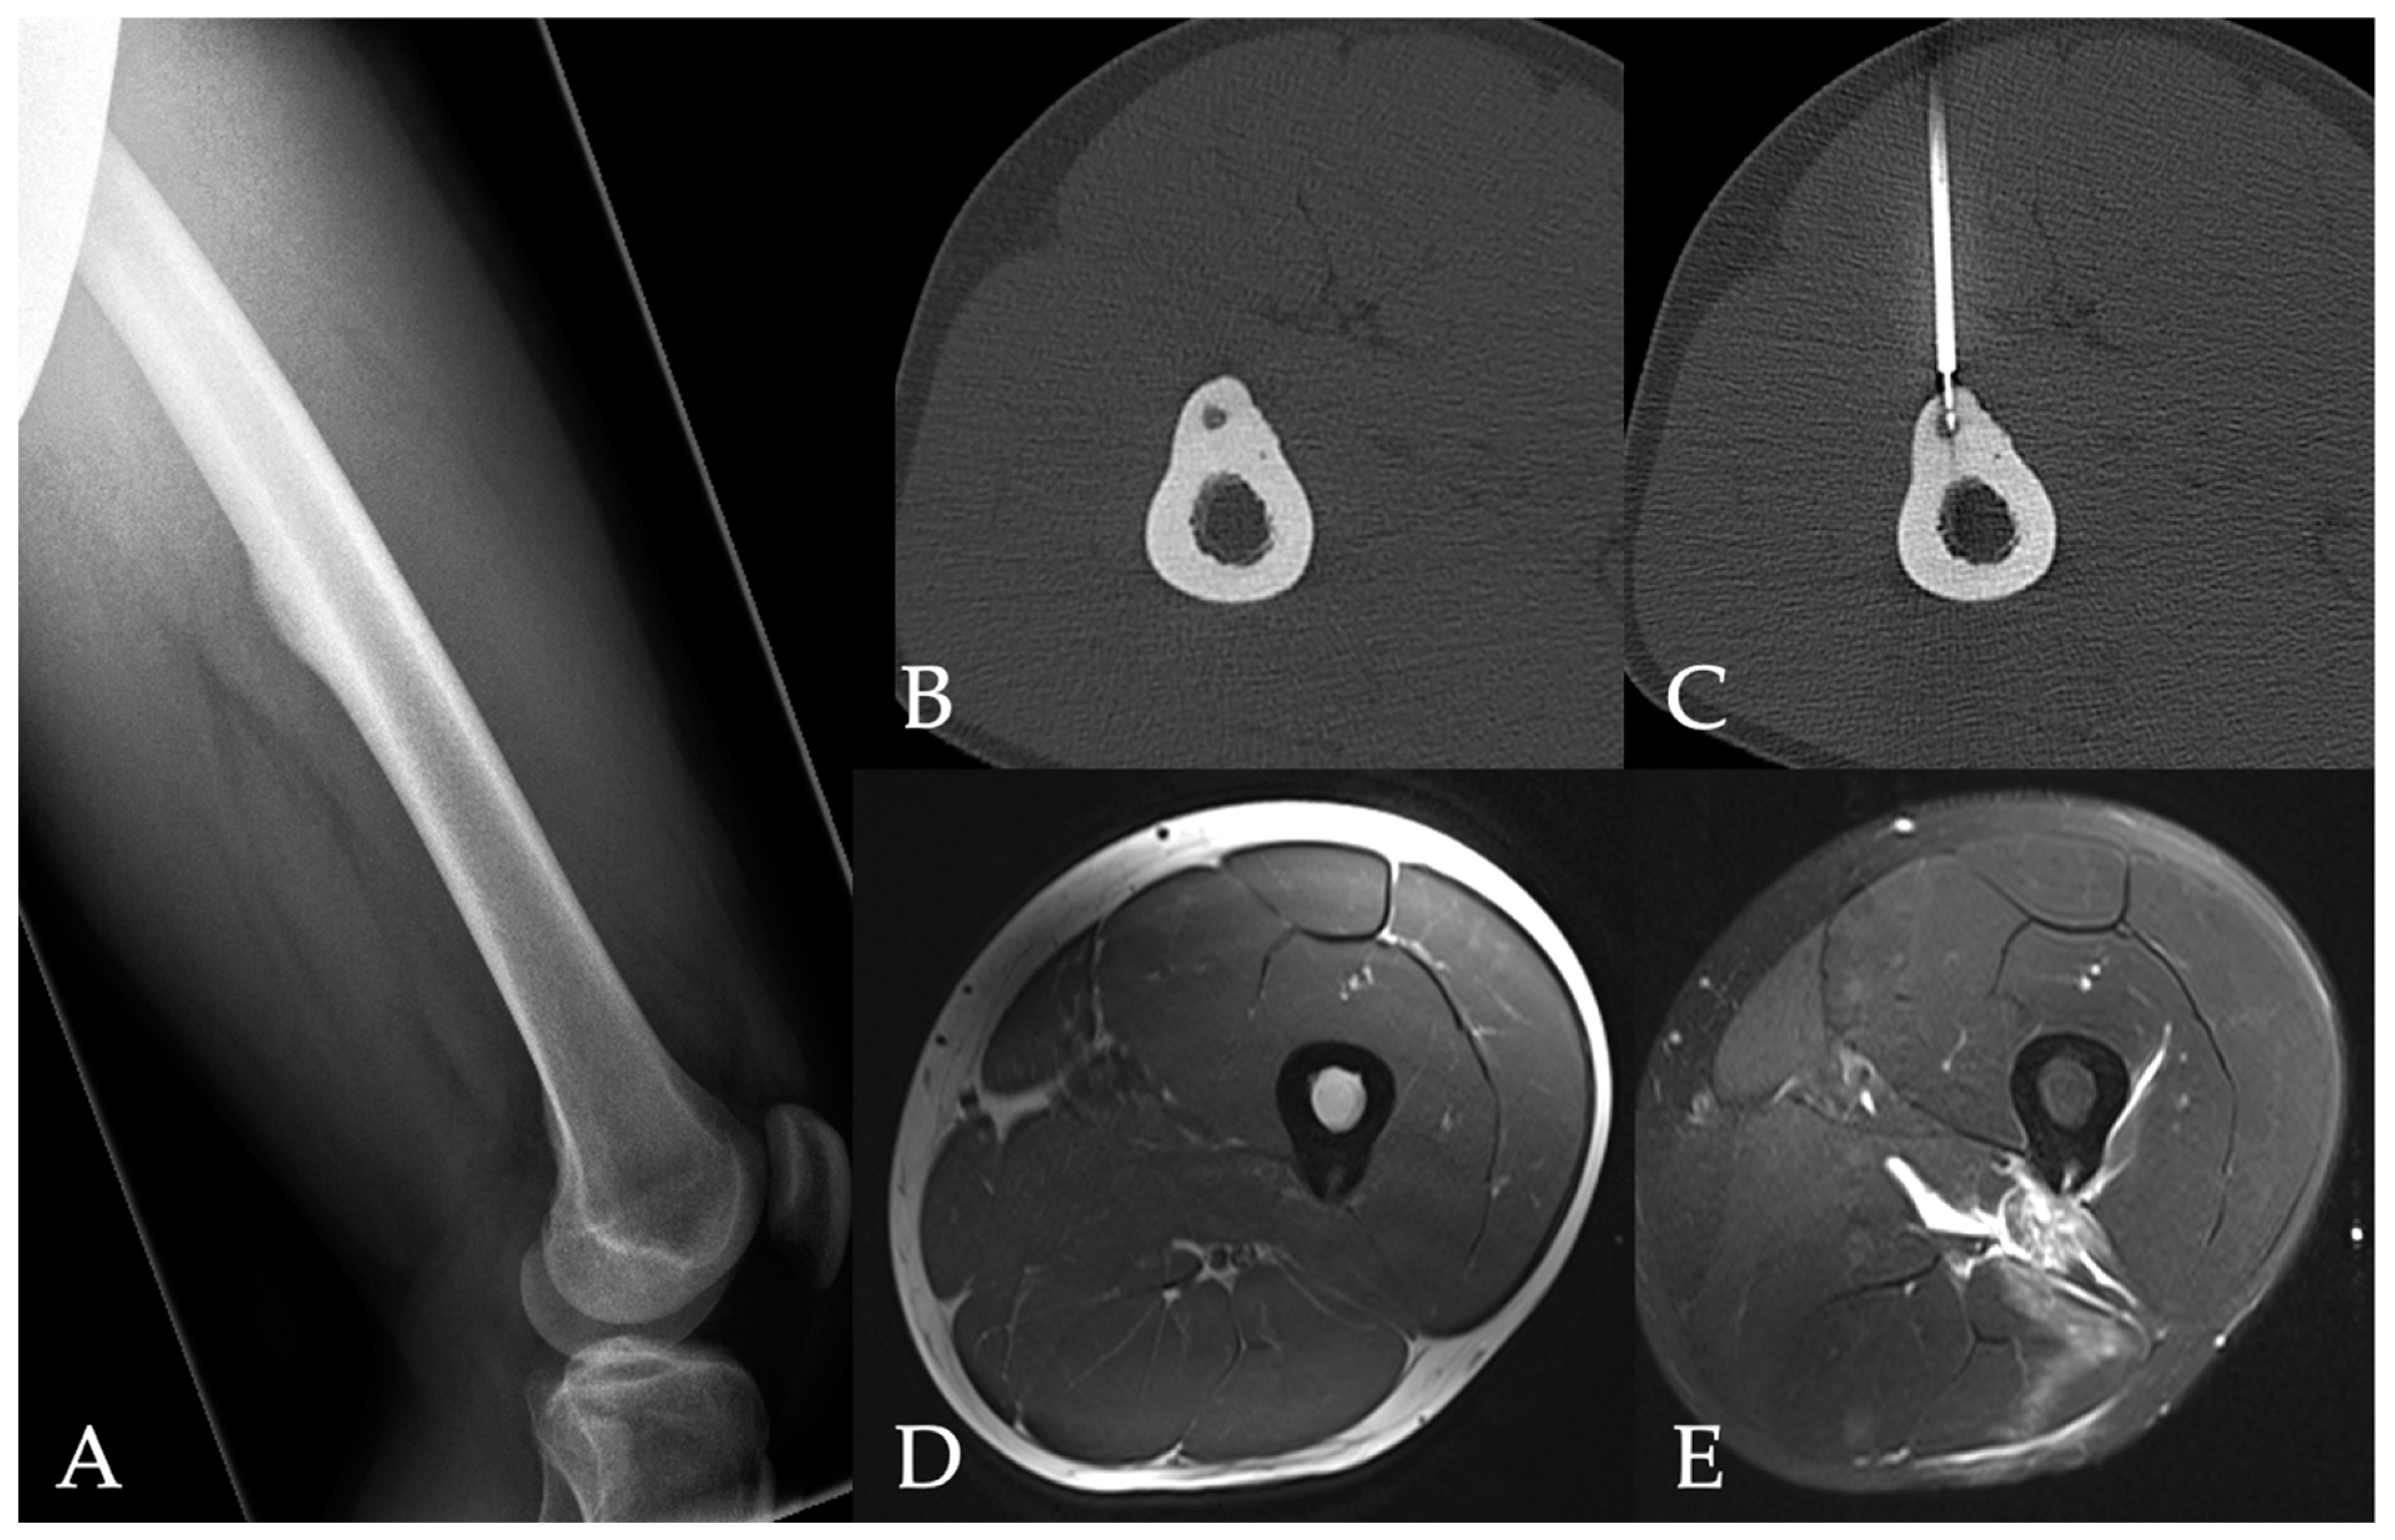

All patients underwent an unenhanced CT scan (Somatom Definition AS, Siemens Healthineers, Forchheim, Germany) of the target region to plan an access path. A bipolar coagulation electrode (Celon Pro Surge micro 150-T09, Olympus Winter & Ibe GmbH, Hamburg, Germany) was placed in the center of the nidus. Following this, the electrode was connected to a power generator (Celon Power System, Celon Lab Precision, Olympus Winter & Ibe GmbH) with an integrated automatic power control that measured tissue resistance. An alternating current field (300–500 kHz) at the tip of the electrode heated the tissue to a target temperature of 60–90 °C. The patients underwent contrast-enhanced MRI for follow-up purposes the day after RFA as well as 3 months after ablation. We noted peri- and post-interventional complications and hospitalization length. Figure 1 and Figure 2 show cases of patients with osteoid osteomas treated by CT-guided bipolar RFA.

Figure 1. 27-year-old male patient with an osteoid osteoma in the femur (A). Peri-interventional CT showing the lesion before and during radiofrequency ablation (B,C). Post-interventional MRI shows post-procedural changes including edema in the soft tissue without damage of the bone structure (D [Axial T1-weighted image], E [axial T2-weighted fat-saturated image]).